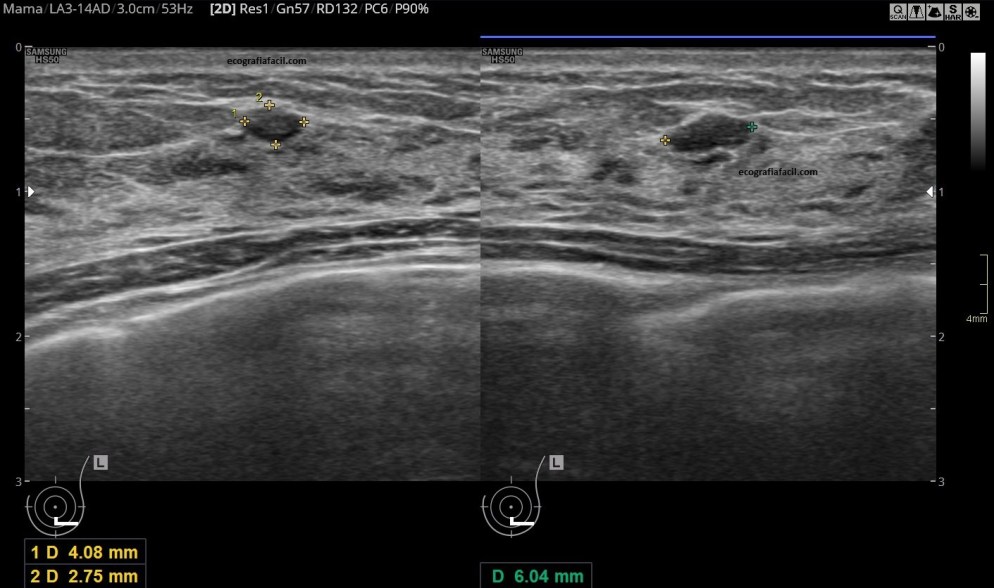

En la imagen 3 y 4 vemos una imagen clarificadora de lo que es una ecografía de mama «normal» y la misma imagen meses después cuando la mama está en proceso de lactancia.

Lo que vemos semiológicamente comparando imagen 3 y 4, es una estructura aumentada de tamaño, más abigarrada y donde observamos que el tejido glandular está aumentadísimo, aumentado también en su hiperfrefringencia, incluso, la lesión que se observa en la imagen 3 se ve como difuminada en la imagen 4…todos esos cambios que se observan claramente en la última imagen.

Conductos dilatados, anecoicos, distribuidos por todo el tejido hiperecogénico típico de esta situación de la lactancia.

In images 3 and 4 we see a clarifying image of what is a «normal» breast ultrasound and the same image months later when the breast is in the process of breastfeeding.

What we see semiologically comparing images 3 and 4, is an enlarged structure, more variegated and where we observe that the glandular tissue is greatly increased, also increased in its hyperfrequency, even, the lesion seen in image 3 is seen as blurred in image 4 … all those changes that are clearly observed in the last image.

Dilated, anechoic ducts, distributed throughout the hyperechogenic tissue typical of this situation of lactation.